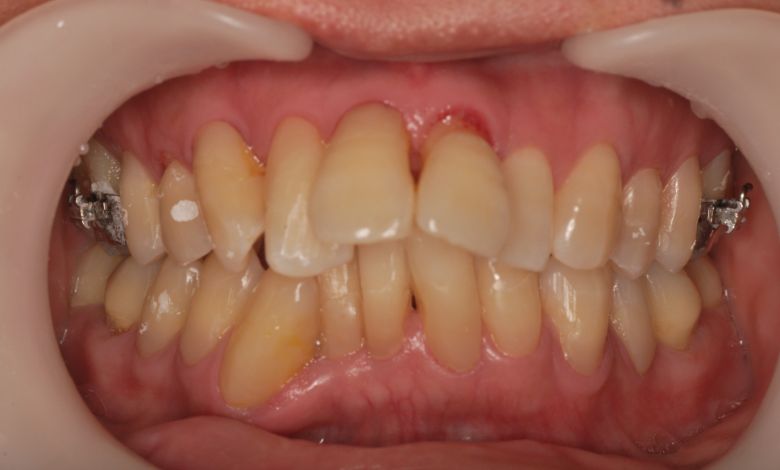

上下顎ともに犬歯が唇側に大きく突出しており、歯列弓が狭小なため、

他院では上下左右4本の便宜抜歯を前提とした矯正治療を提案されていました。

上顎には左右の犬歯が著しく唇側に偏位している

精密検査の結果、当院では抜歯を行わず、歯列弓の拡大によってスペースを確保し、非抜歯での矯正治療を選択しました。歯列の叢生(ガタガタ)は解消され、機能的かつ審美的に優れた咬合が得られました。